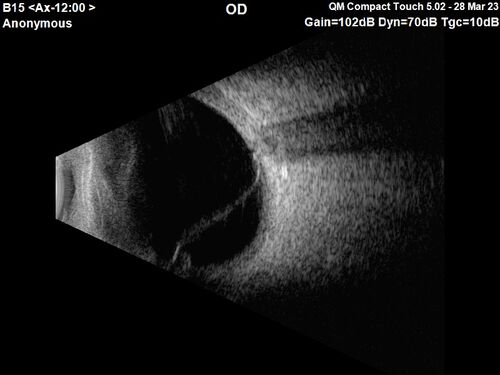

Choroidal Metastatic Breast Cancer with Exudative Detachment

58 year old female presented with 20/200 vision. Had 10 sessions of radiation and tumor shrank. The exudative detachment took almost a year to resolve. The vision improved to 20/40.